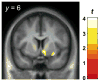

Results: IV EtOH induced significant increases in DA in the right ventral striatum in NTS, but not SD. No decreases in DA were observed in either group.

Conclusions: Alcohol intoxication results in distinct anatomic profiles of DA responses in SD and NTS, suggesting that in NTS, the striatal DA system may process effects of alcohol intoxication differently than in SD.